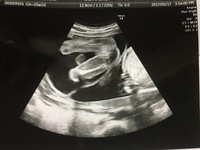

妊娠6ヶ月 21年03月31日 (水) 21時11分22秒 テーマ: 第5子妊娠中 赤ちゃんとっても順調に育っていました 右下のお腹ばっかり蹴るな〜と思ったら、やっぱり逆子ちゃんでした。 まだグルグル回るだろうから、逆子体操しなくて大丈夫だけど、心配なら胎動が最も活発なのは妊娠7~8ヶ月頃 胎動は 妊娠6ヶ月頃には多くのママたちが体感できる ようになってきます。 妊娠9ヶ月での逆子のリスクはある? ママハピライフ管理人 年6月26日 / 21年1月1日 赤ちゃんが逆子の状態かどうかは病院のエコー検査だけでなく、胎動によっても知ることがで

1ヶ月ぶりに6回目の妊婦検診へ行ってきたのですが、、、 逆子 になっていました〜💦💦💦💦 お腹の下あたりをキックされてたのは逆子が原因だったのね😭無知だったから何も疑問に思わずに過ごし妊娠中の首肩こりって、つわりが原因なの? 産後の骨盤矯正ってどれを受けてもいいの? 妊娠9ヶ月目、腰痛と骨盤痛で悩んでいました。 妊娠5~6ヶ月目の期間中に逆子が改善した♪; こんにちは! 妊活・妊娠情報サイト「ももいろファミリー」のももです。 現在妊娠7ヶ月、お腹の赤ちゃんは26週です。 妊娠中期の逆子診断 直近の妊婦健診に行ったところ、エコー検査でなんと 逆子ですね〜。

妊娠6ヶ月 妊娠週 21週 22週 23週 妊娠中期 の超音波写真 妊娠 出産 育児に関する総合情報サイト ベビカム